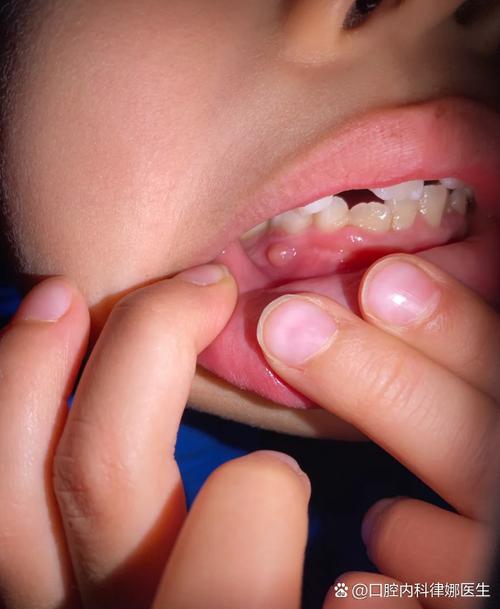

- 特点:牙龈红肿、松软、容易出血,有时会形成一个或多个鲜红色或暗红色的、质地柔软的息肉状小疙瘩,孩子可能不会觉得疼,但刷牙或吃东西时容易出血。

萌出性牙龈囊肿 (Eruption Cyst) - 常见于长牙期

这是乳牙或恒牙快要萌出时,牙齿上方的牙龈组织内形成的充满液体或血液的囊肿。

- 特点:通常出现在即将长牙的牙龈位置,是一个蓝色或紫色的、半透明的小水疱或肉疙瘩,大小像一颗小豌豆,它通常不疼,随着牙齿萌出会自行破裂消失。